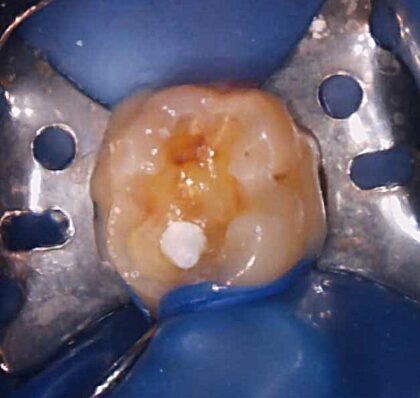

むし歯を検知液で染め出しながら慎重に除去していくと、案の定神経まで達し歯の中から出血が見られました。

消毒を繰り返しながら止血を試みると、健全な神経が存在していたので、神経を保護する薬を中においてコンポジットレジンで封鎖しました

しばらく経過を見てから歯を作っていく予定です。